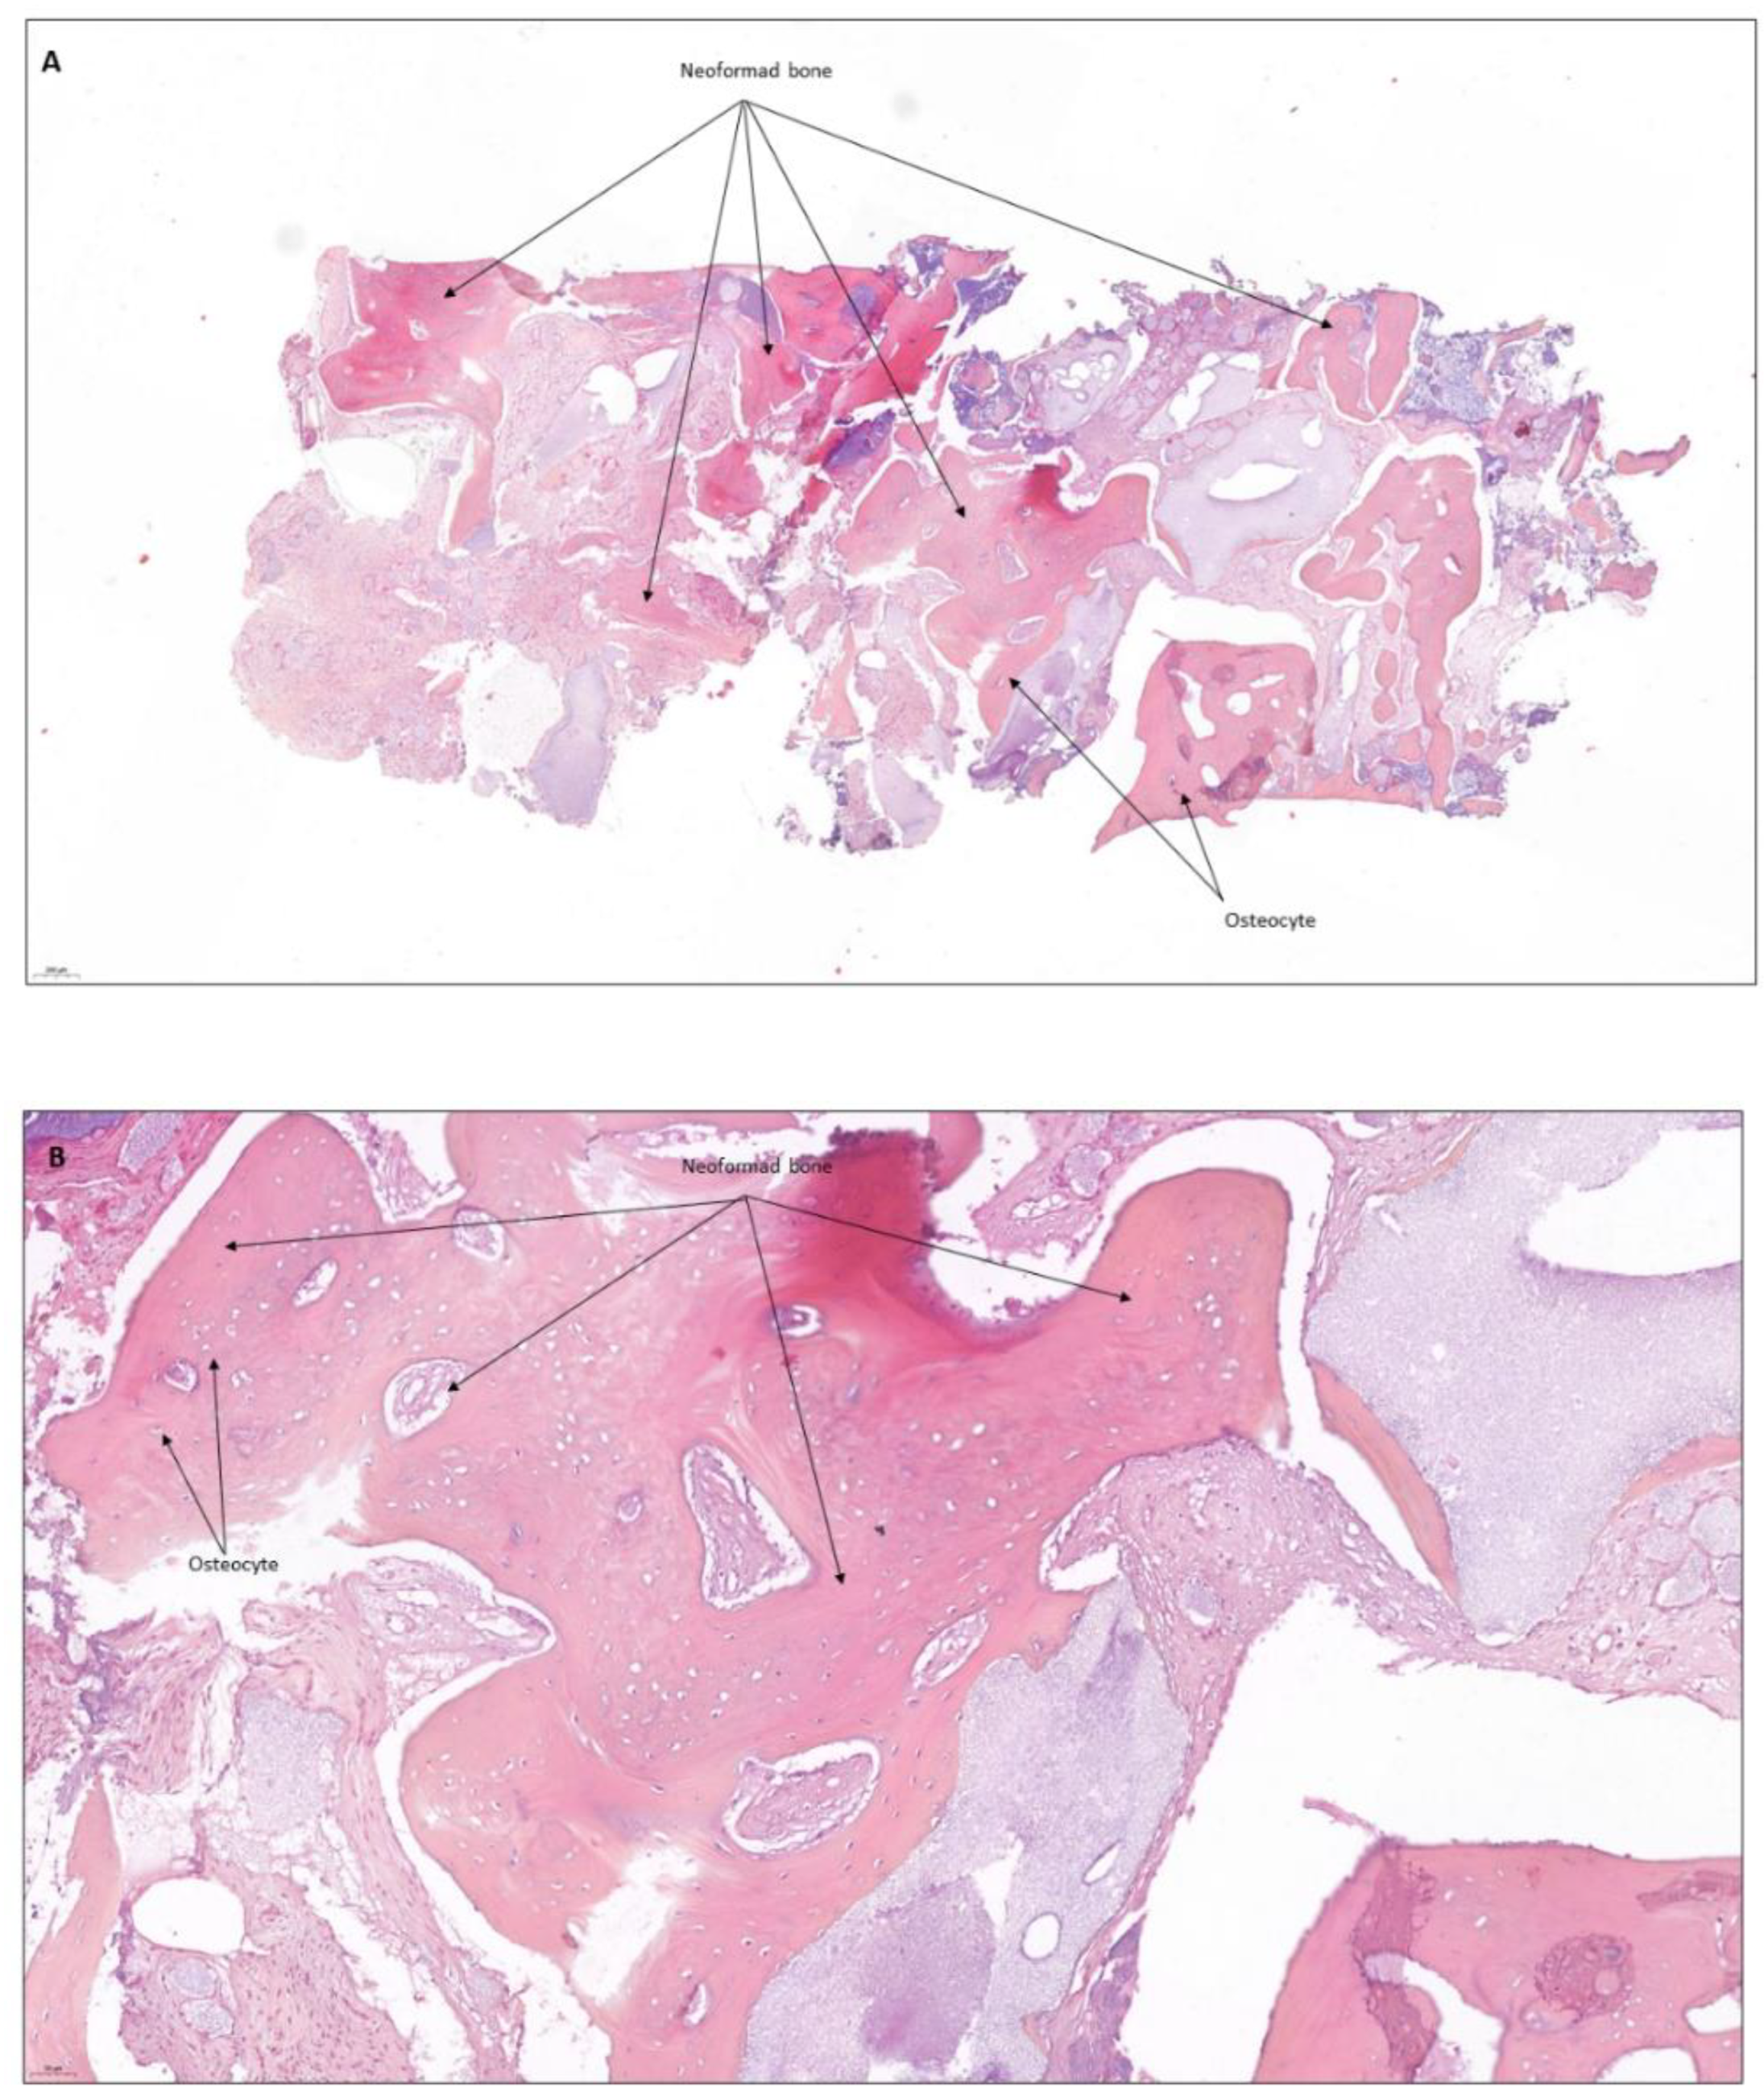

4. Clinical Cases

4.1. Patient No. 1

4.2. Patient No. 2

4.3. Patient No. 3

4.4. Patient No.4

4.5. Patient No.5

4.6. Patient No.6